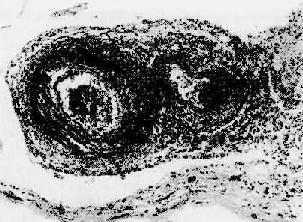

图4-12 红斑性狼疮之脾病变

脾小体中央细动脉壁呈洋葱皮样结构